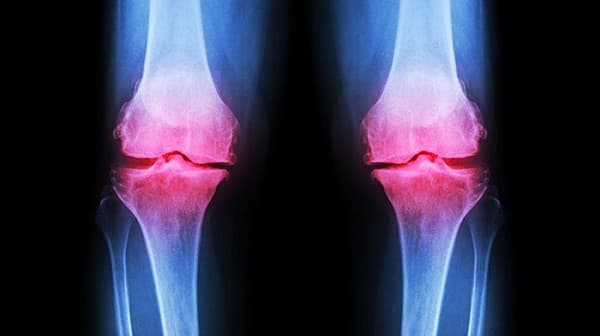

- Thoái hóa khớp gối phổ biến nhất (ảnh minh họa)

Theo WHO, thoái hóa khớp là nguyên nhân gây tàn tật phổ biến nhất ở người lớn tuổi. chiếm 50% toàn bộ gánh nặng bệnh cơ xương khớp. Ước tính trên toàn thế giới có khoảng 9,6% nam giới và 18,0% phụ nữ trên 60 tuổi bị thoái hóa khớp có triệu chứng. Nếu như trước đây, thoái hóa khớp được coi là căn bệnh của người già thì hiện nay, không ít người khoảng hơn 20 tuổi đến 30 tuổi đã bị thoái hóa khớp.